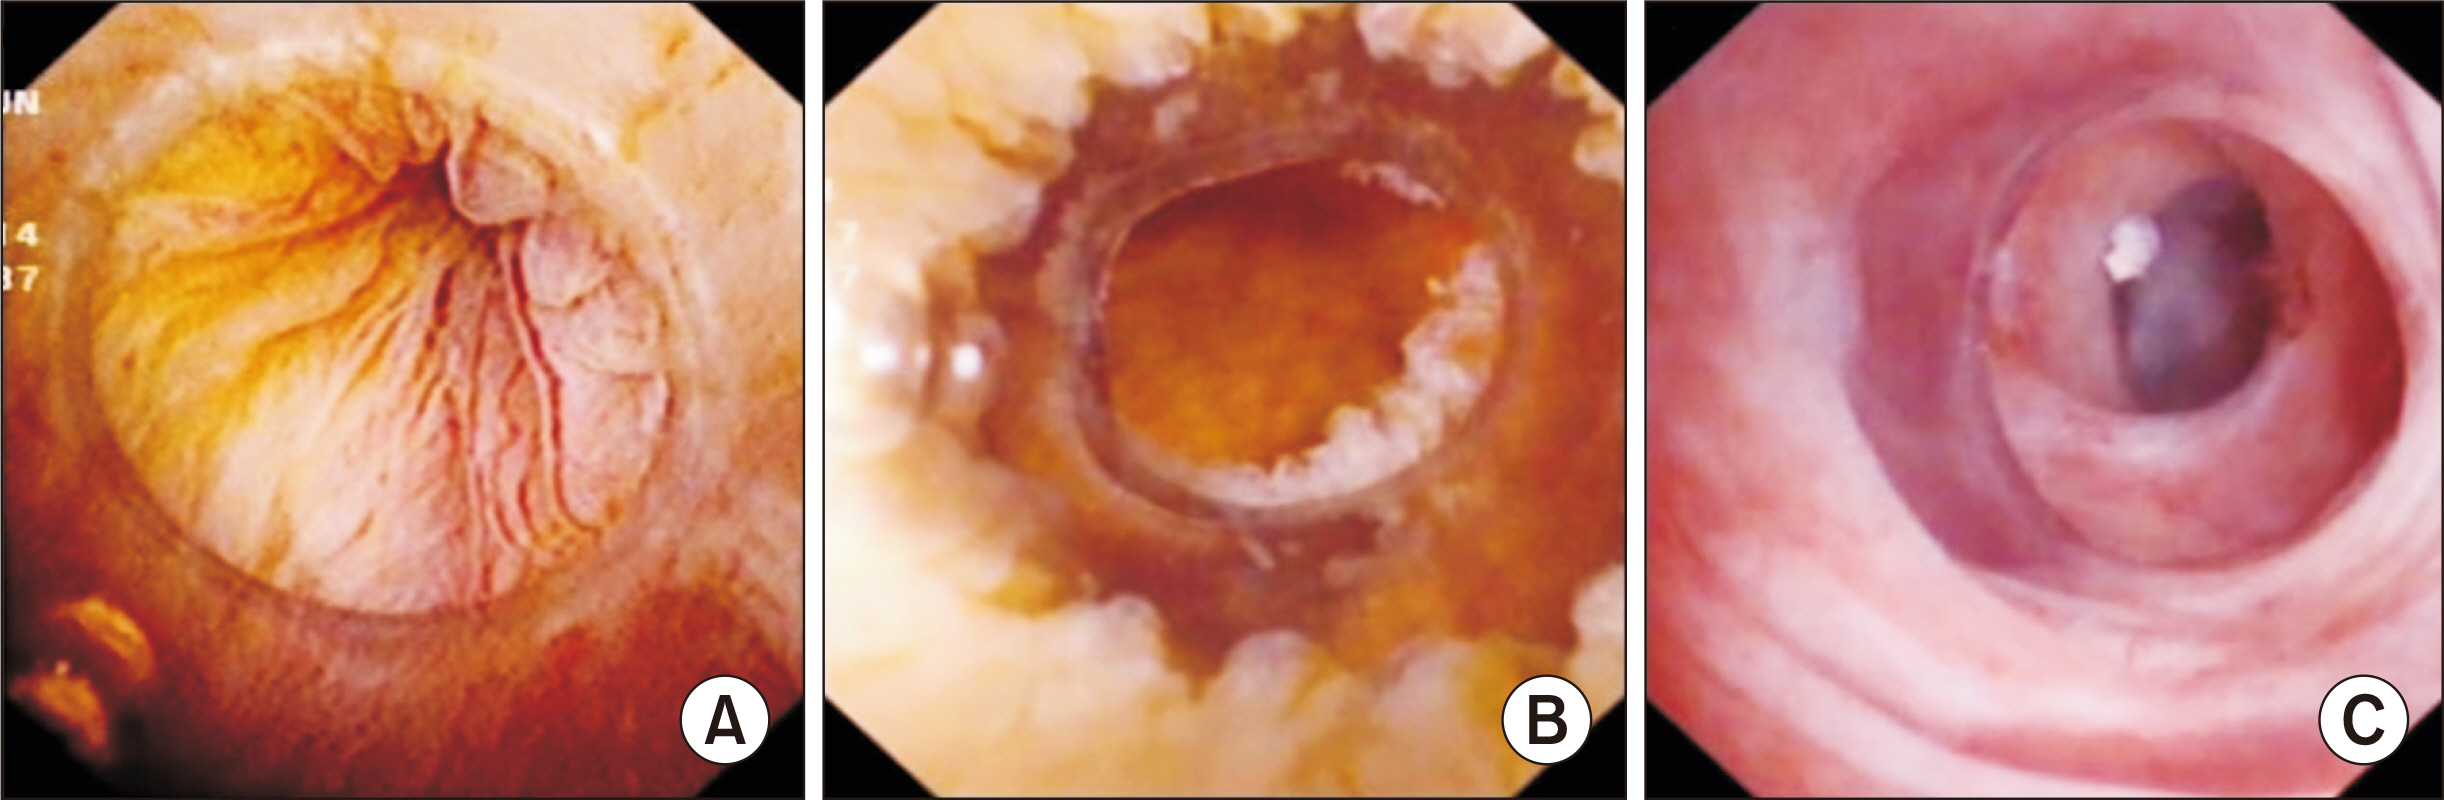

- Laparoscopic subtotal cholecystectomy (LSC) has been a safe and viable alternative to conversion to laparotomy in cases of severe cholecystitis. The objective of this study is to determine the utility of intraoperative choledochoscopy in LSC for the exploration of the gallbladder, cyst duct, and subsequent stone clearance of the cystic duct in cases of severe cholecystitis. A total of 72 patients diagnosed with severe cholecystitis received choledochoscopy-assisted laparoscopic subtotal cholecystectomy (CALSC). A choledochoscopy was performed to explore the gallbladder cavity and/or cystic duct, and to extract stones using a range of techniques. The clinical records, including the operative records and outcomes, were subjected to analysis. No LSC was converted to open surgery, and no bile duct or vascular injuries were sustained. All stones within the cystic duct were removed by a combination of techniques, including high-frequency needle knife electrotomy, basket, and electrohydraulic lithotripsy. A follow-up examination revealed the absence of residual bile duct stones, with the exception of one common bile duct stone, which was extracted via endoscopic retrograde cholangiopancreatography. In certain special cases, CALSC may prove to be an efficacious treatment for the management of severe cholecystitis. This technique allows for optimal comprehension of the situation within the gallbladder cavity and cystic duct, facilitating the removal of stones from the cystic duct and reducing the residue of the non-functional gallbladder remnant.

Figure